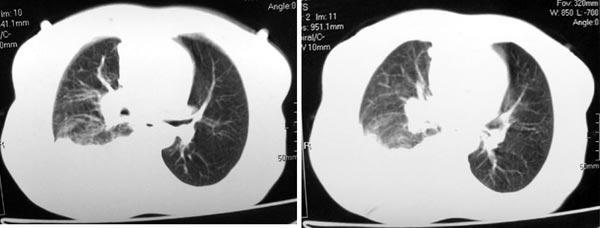

图像不是太好,但可以见到下列恶性征象:

1 单侧肺门增大

2 纵隔侧胸膜明显增厚

3 肋胸膜结节影

结合纵隔略宽、单侧胸水首先考虑肺癌。

右侧胸膜结节状增厚伴胸腔积液及纵隔、腋窝淋巴结肿大,考虑胸膜间皮瘤可能性大;建议胸膜活检。

右侧中央型肺癌合并阻塞性肺炎及右侧胸膜转移。

右侧肺门淋巴结肿大,伴大量胸腔积液,同侧胸膜结节样增厚,有胸膜粘连,考虑肺癌.